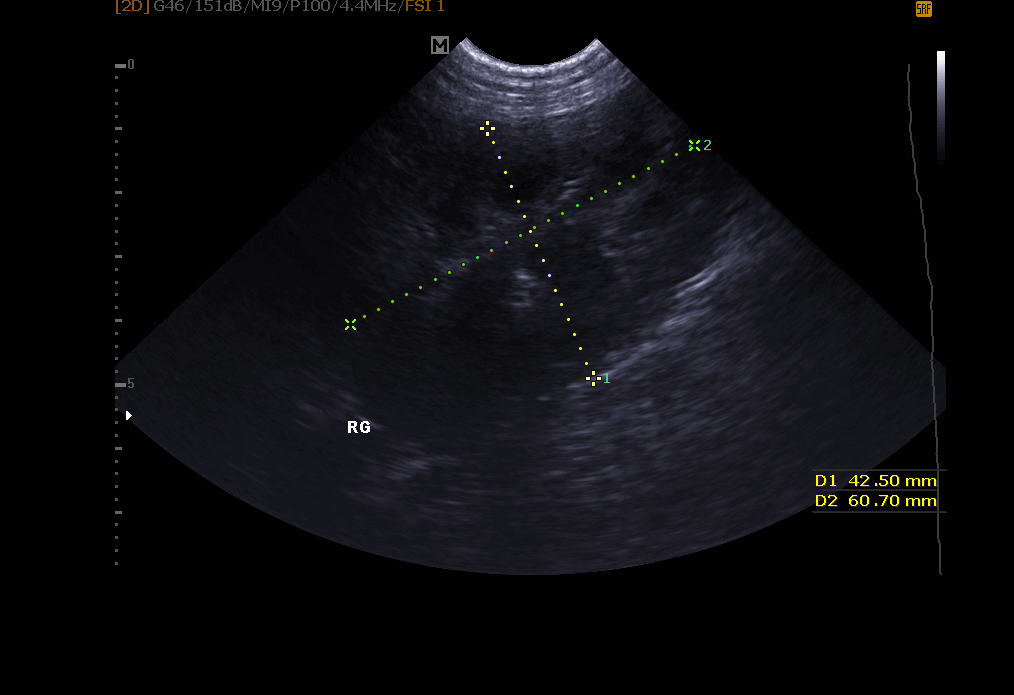

Echographie abdominale: elle permet l’exploration de le vessie (recherche de calculs, polypes, tumeur), des reins, de la rate , du foie , du pancréas et autres organes abdominaux.

Examen de l’appareil génital: infection de l’utérus, gestation détectable dés 18 à 21 jours chez la chatte et la chienne, kystes ovariens, exploration de la prostate chez le mâle.